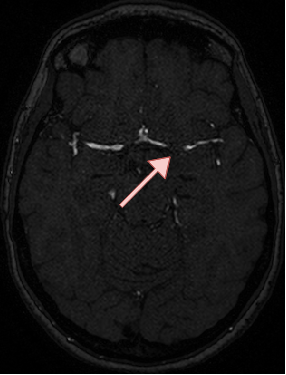

4.4 Qualitative Results

We show sample visual results of representative slices in Figure 3. Sample 3D visual results are given as surface renderings of segmentation maps in Figure 4.